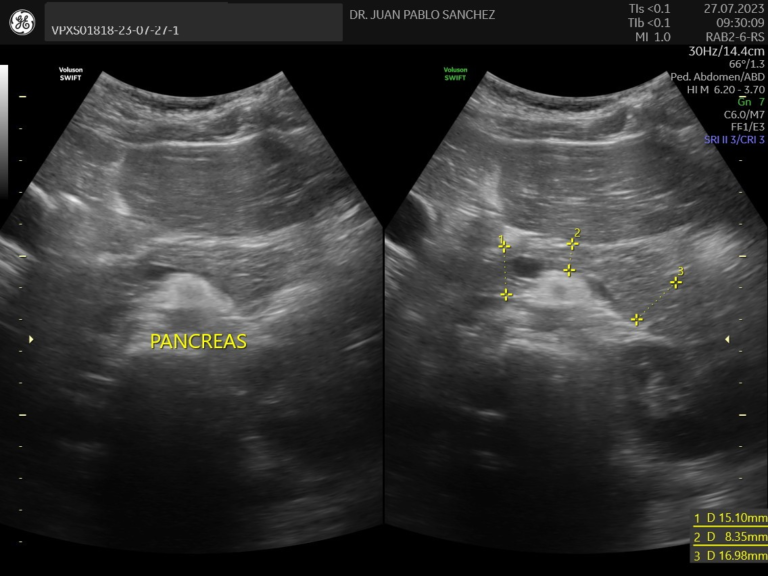

Ecografia abdominal

Estudio no invasivo que permite observar los órganos del abdomen, como el hígado, riñones, intestinos, vejiga, etc. Es útil para detectar infecciones, malformaciones o dolores sin usar radiación ni dolor.